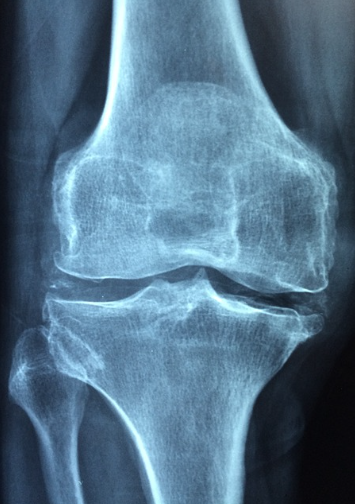

영상 검사: X-ray나 MRI를 통해 슬개골과 주변 구조를 확인하여 슬개골연골연화증 여부를 판단합니다.